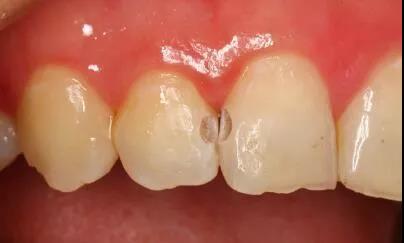

这些酸对牙齿外层的牙釉质具有酸蚀作用,由此牙齿开始变色,时间一长甚至会形成蛀牙龋洞。

▶ 被“蛀出洞”的牙齿

牙齿邻接处变色

牙齿邻接处缺损,出现龋洞